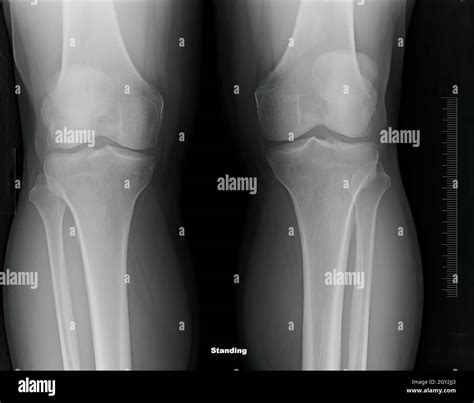

Healthy Knee Xrays

Interpreting Healthy Knee X-rays

Interpreting knee X-rays requires a trained eye. Here are some key features that radiologists look for in Healthy Knee X-rays:

• Bone Structure: The bones of the knee, including the femur, tibia, and patella, should appear smooth and intact without any fractures or deformities.

• Joint Space: The space between the bones should be uniform and not narrowed, which can indicate wear and tear or arthritis.

• Soft Tissue: While X-rays primarily show bone, the soft tissue around the knee should appear normal without any signs of swelling or inflammation.

• Alignment: The knee joint should be properly aligned, with no signs of dislocation or misalignment.